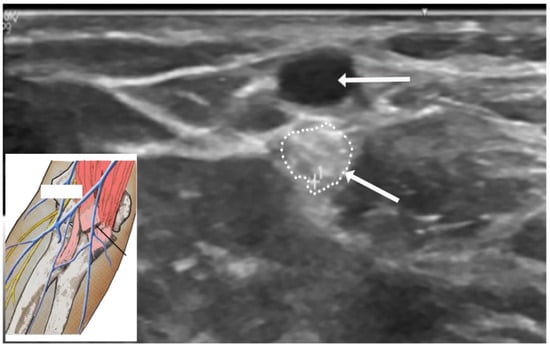

4.5. Ultrasound Studies

US studies may assist in the diagnostic evaluation of LACN neuropathy by differentiating various conditions with symptoms involving the upper arm, elbow, forearm, and wrist [35]. Ultrasound (US) plays an important role in the localization and determination of the etiology of LACN neuropathy. In Chiavaras and colleagues’ study of USs of the LACN with MRI and anatomic correlation in 13 patients with LACN neuropathy, the symptomatic LACN demonstrated fusiform enlargement, increased echogenicity, and loss of the normal fascicular echotexture [35]. The mean cross-sectional area of the symptomatic LACN was 12.0 mm2 compared to 3.3 mm2 at the same level in the contralateral normal side. While only seven patients in our series underwent an US study, it was valuable in providing details of the masses in the upper extremity compressing the LACN. Figure 5 depicts the US study involving injury to the LACN from phlebotomy.

Figure 5.

Ultrasound of injury to the lateral antebrachial cutaneous nerve from phlebotomy. Horizontal arrow points to the cephalic vein. Oblique arrow points to enlarged and hyperechoic lateral antebrachial cutaneous nerve. Oblique arrow points to the enlarged and hyperechoic lateral antebrachial cutaneous nerve (encircled by small dots).